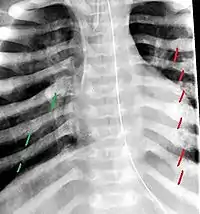

The material factual allegations of the amended complaint are as follows. Plaintiff was born on May 14, 1970. On repeated occasions during the first year of her life she was severely beaten by her mother and the latter's common law husband, one Reyes. On April 26, 1971, when the plaintiff was eleven months old, her mother took her to the San Jose Hospital for examination, diagnosis, and treatment. The attending physician was defendant Dr. Flood, acting on his own behalf and as agent of the defendant San Jose Hospital. At the time, the plaintiff was suffering from a comminuted spiral fracture of the right tibia and fibula, which gave the appearance of having been caused by a twisting force. Plaintiff's mother had no explanation for this injury. Plaintiff had bruises over her entire body. In addition, she had a non-depressed linear skull fracture which was then in the process of healing. Plaintiff demonstrated fear and apprehension when approached. Inasmuch as all plaintiff's injuries gave the appearance of having been intentionally inflicted by other persons, she exhibited the medical condition known as the battered child syndrome.

The complaint avers that as a proximate result of the foregoing negligence plaintiff was released from the San Jose Hospital without proper diagnosis and treatment of her battered child syndrome, and was returned to the custody of her mother and Reyes who resumed physically abusing her until she sustained traumatic blows to her right eye and back, puncture wounds over her left lower leg and across her back, severe bites on her face, and second and third degree burns on her left hand.

On July 1, 1971, plaintiff was again brought in for medical care, but to a different doctor and hospital. Her battered child syndrome was immediately diagnosed and reported to local police and juvenile probation authorities, and she was taken into protective custody. Following hospitalization and surgery she was placed with foster parents, and the latter subsequently undertook proceedings to adopt her. Plaintiff's mother and Reyes fled the state, but were apprehended, returned for trial, and convicted of the crime of child abuse.[3]

On this appeal plaintiff has expressly abandoned her claim of punitive damages. It is alleged that proper diagnosis of plaintiff's condition would have included taking X-rays of her entire skeletal structure, and that such procedure would have revealed the fracture of her skull. Defendants negligently failed to take such X-rays, and thereby negligently failed to diagnose her true condition. It is further alleged that proper medical treatment of plaintiff's battered child syndrome would have included reporting her injuries to local law enforcement authorities or juvenile probation department. Such a report would have resulted in an investigation by the concerned agencies, followed by a placement of plaintiff in protective custody until her safety was assured. Defendants negligently failed to make such report. The complaint avers that as a proximate result of the foregoing negligence plaintiff was released from the San Jose Hospital without proper diagnosis and treatment of her battered child syndrome, and was returned to the custody of her mother and Reyes who resumed physically abusing her until she sustained traumatic blows to her right eye and back, puncture wounds over her left lower leg and across her back, severe bites on her face, and second and third degree burns on her left hand.